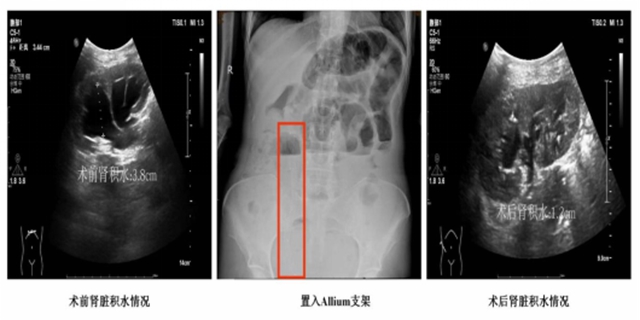

手术在微创内镜下进行。医生通过膀胱镜,精准地将堵塞的旧支架取出,然后将新的覆膜支架沿导丝置入到被肿瘤堵塞的输尿管段。整个过程创伤小,恢复快,效果立竿见影。

术后当天, 李女士的尿液就通过支架顺畅地流入膀胱,腰背剧痛迅速缓解;术后三天, 她的肾功能指标(肌酐)逐步下降至接近正常水平。最关键的是, 她腰间的肾造瘘管被成功拔除!她终于可以自由地洗澡、翻身,不再需要时刻担心身上的导管。

出院后, 李女士的生活质量得到了巨大提升。她能够更好地接受后续的肿瘤治疗,也有了更多与家人相处的宝贵时光。在后续的复查中,支架位置良好,引流通畅,没有再发生堵塞。